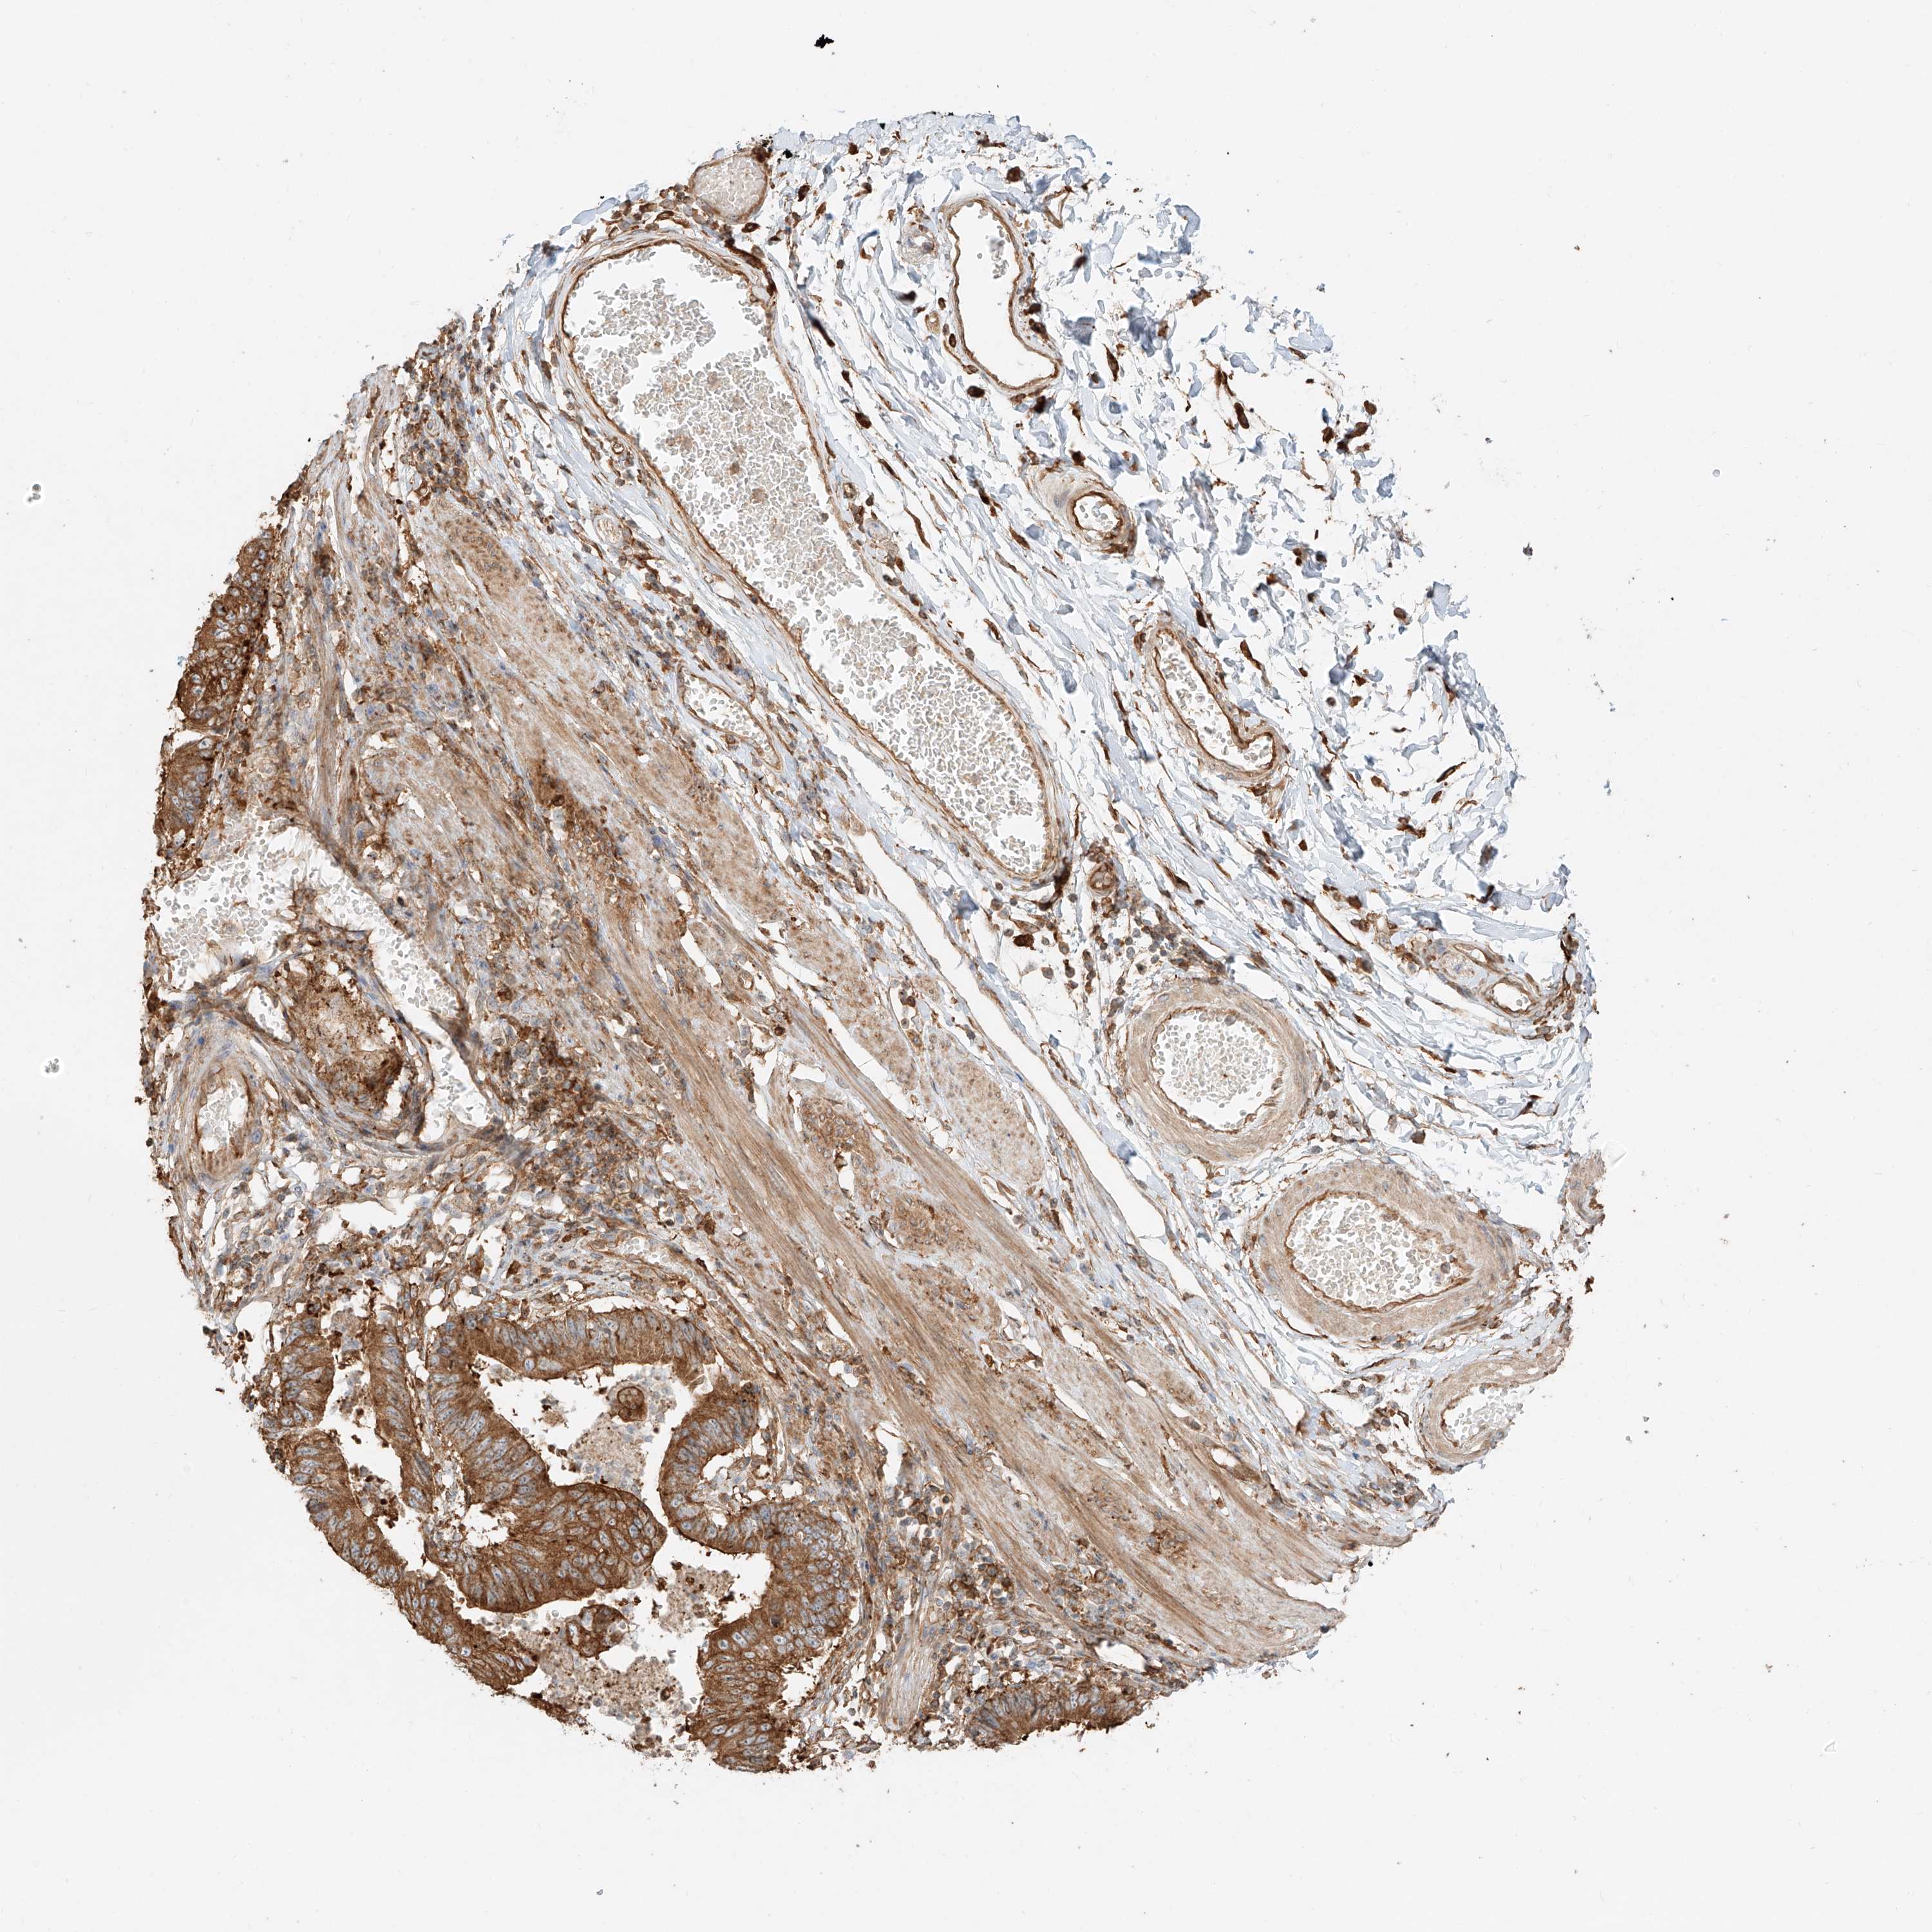

STOMACH CANCER - Protein expressioni

A mouse-over function shows sample information and annotation data. Click on an image to view it in a full screen mode. Samples can be filtered based on level of antibody staining by selecting one or several of the following categories: high, medium, low and not detected. The assay and annotation is described here.

Note that samples used for immunohistochemistry by the Human Protein Atlas do not correspond to samples in the TCGA dataset.

Antibody stainingi

Antibody staining in the annotated cell types in the current human tissue is reported as not detected, low, medium, or high, based on conventional immunohistochemistry profiling in selected tissues. This score is based on the combination of the staining intensity and fraction of stained cells.

Each image is clickable and will lead to virtual microscopy that enables deeper exploration of all samples and also displays staining intensity scores, fraction scores and subcellular localization as well as patient and tissue information for each sample.

Antibody HPA031410

Staining

High

Medium

Low

Not detected

Intensity

Strong

Moderate

Weak

Negative

Quantity

>75%

75%-25%

<25%

None

Location

Nuclear

Cytoplasmic/membranous

Cytoplasmic/membranous,nuclear

Adenocarcinoma, NOS